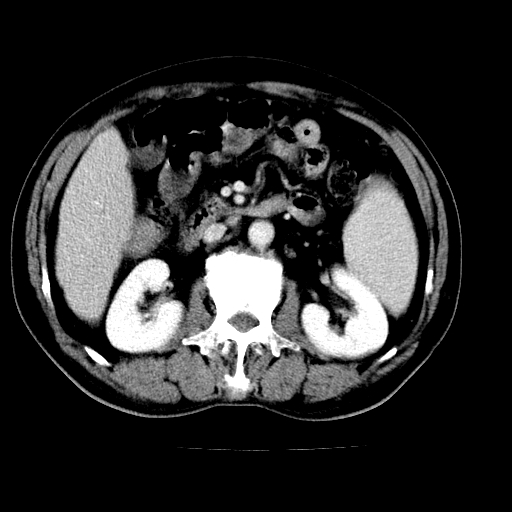

男,66岁,上腹部不适、黄染一周。彩超示:肝左叶占位,肝内胆管扩张,胆总管扩张,胆总管占位?

肝左叶不规则软组织肿块影,边缘不规整邻近肝实质受累分界不清;肝内胆管(左叶)明显扩张成“软藤状”,诊断:肝左叶胆管细胞癌。

肝左叶占位性病变,并胆管扩张,符合胆管细胞癌ct表现,门脉左支受累,左肾囊肿。窗宽太窄了,其他的看不清

左叶胆管细胞癌累及胆总管,门脉左支受侵,慢性胆囊炎胆结石,左肾小囊肿